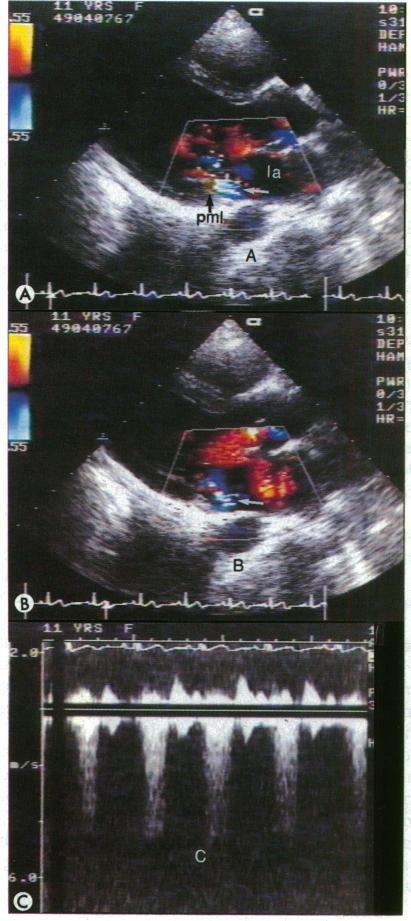

无明显心脏炎的急性风湿热中瓣膜性心脏病的发生:彩色多普勒识别

Occurrence of valvar heart disease in acute rheumatic fever without evident carditis: colour-flow Doppler identification.

To determine the frequency of occurrence of mitral and aortic valvar regurgitation in rheumatic children in whom there was no evidence of carditis acutely or at an earlier attack.

Colour flow Doppler imaging was used in a non-randomised study of sequentially admitted children who met the criteria for acute rheumatic fever without clinically evident carditis and patients in whom the disease was quiescent after a previous attack of rheumatic fever. Two separate control groups were used for comparison of the echocardiographic findings, and a group of patients with confirmed rheumatic carditis was included for comparison of acute phase and antistreptococcal reactants.

Mitral or mitral and aortic regurgitation was found in 10 of the 11 children studied in the acute rheumatic period. None had a murmur or other evidence of carditis. In all the cases studied the valvar insufficiency was mild. Four of the children studied late in the quiescent period had either aortic or mitral insufficiency by colour flow Doppler evaluation; two children who had previously had valvar insufficiency no longer showed this, and one child without positive findings in the acute phase remained without insufficiency. None of the non-rheumatic control subjects showed mitral or aortic regurgitation.

Colour flow Doppler imaging is a useful method of identifying subclinical mitral and aortic valvar disease at all stages of rheumatic fever when carditis cannot be otherwise detected and is a valuable addition to current diagnostic criteria.